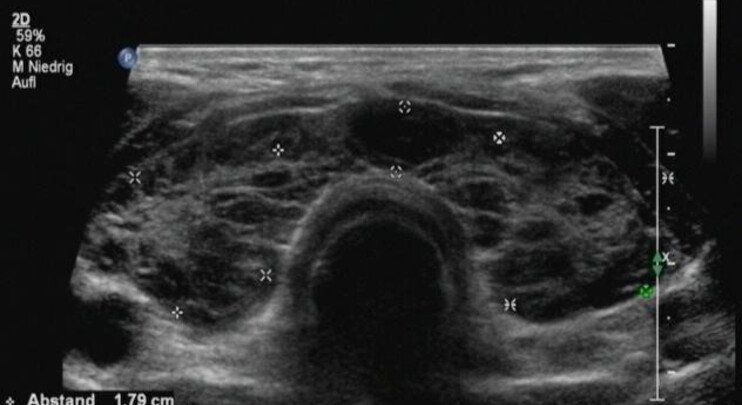

Schilddrüsen-Sonographie

Die Schilddrüsen-Sonographie zeigt die Struktur und Größe der Schilddrüse. Knoten, Zysten oder Entzündungen können präzise festgestellt werden. Diese Untersuchung ist sanft, strahlenfrei und liefert wichtige Informationen für die Diagnose und Kontrolle von Schilddrüsenerkrankungen.